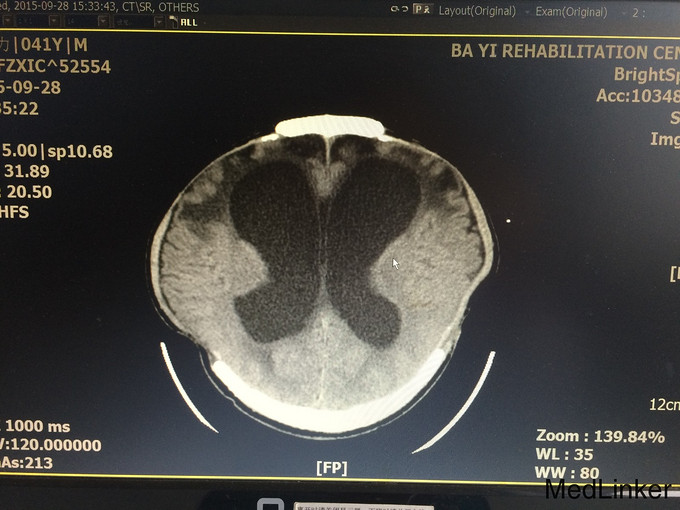

入院查体:气管切开,自带鼻饲管,生命体征稳定:脉搏 70次/分,血压121/71mmHg;Glasgow昏迷评分9分,最小意识状态;双侧颅骨缺如;四肢肌张力增高,肌力1-2级,左上肢肘关节活动受限。 辅查:血常规、肝肾功、凝血、电解质、血脂、血糖均正常;头颅MRI(2015.09.17)示:双侧额颞叶及右侧枕顶叶片状低密度影;交通性脑积水;双侧颞额顶骨部分缺如,相邻脑组织膨出,多系术后改变;头颅MRI(2015.09.28)示:与前面的片子比较,变化不大;

诊断:重型颅脑损伤 双侧额叶脑挫裂伤;双侧额颞顶部硬膜下血肿;脑疝形成;最小意识状态。 入院后治疗上积极给以神经营养、床旁康复治疗,高压氧治疗20天促醒;预防肺部感染;预防癫痫发作;

患者病情好转缓慢,2周前强直阵挛发作一次;影像资料提示颅内情况并未明显改善。请神经外科会诊后,建议作脑脊液侧脑室腹腔分流术。对于有脑积水的患者,不排除越早行脑脊液分流术,意识障碍恢复的时间就越短,效果就越好!另外,高压氧治疗方面,怎样发挥出最佳的治疗效果?